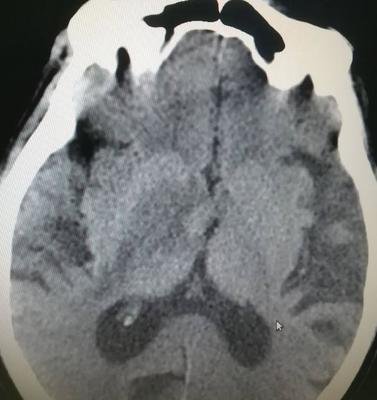

腦萎縮是指由各種原因?qū)е履X組織本身發(fā)生器質(zhì)性病變而產(chǎn)生萎縮的一種現(xiàn)象。病理上表現(xiàn)為腦組織體積縮小,細胞數(shù)目減少,腦室和蛛網(wǎng)膜下腔擴大。對患者的正常生活造成極大的影響。那么腦萎縮的原因的癥狀有哪些呢?

其實,隨著年齡增加,腦組織會出現(xiàn)一定程度的萎縮,這是正常生理現(xiàn)象。如果萎縮過快、過早就是疾病導(dǎo)致的,比如腦梗、腦出血或者因為車禍外傷等導(dǎo)致腦部創(chuàng)傷,也容易出現(xiàn)腦萎縮。神經(jīng)系統(tǒng)的變性性疾病,比如阿爾茨海默病、路易體癡呆、帕金森病導(dǎo)致的癡呆,還有額、顳葉變性也容易導(dǎo)致患者出現(xiàn)腦萎縮。